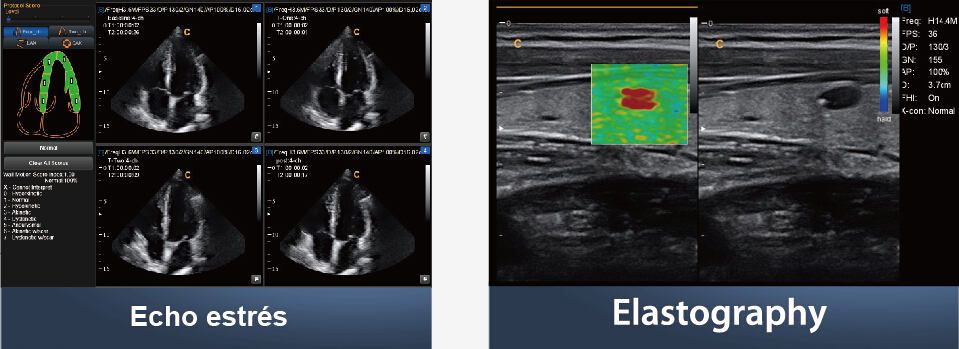

● Echo estrés